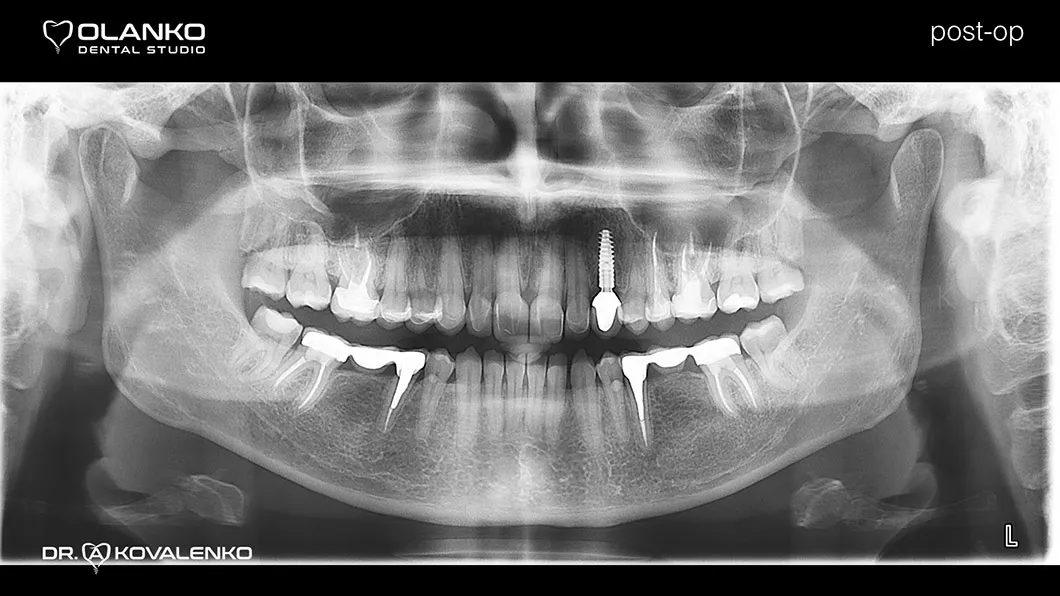

Клинический случай 3 протезирование

Пациентка обратилась с жалобами на неудовлетворительную эстетику, наличие промежутков между зубами (тремы, диастемы) полное отсутствие (адентия бокового резца слева).

Диагностика: эстетический анализ, создание проекта новой улыбки DSD (цифровой дизайн улыбки).

Лечение: замена старых несостоятельных композитных реставраций и лечение кариеса, повторное лечение каналов с использованием микроскопа в 3х зубах.

Установлен зубной имплантат в области 23 зуба.

Проведена хирургическая коррекция десневого контура в области фронтальных зубов.

Протезирование:12 керамических реставраций (коронки,виниры на зубах и имплантате) на верхней челюсти.